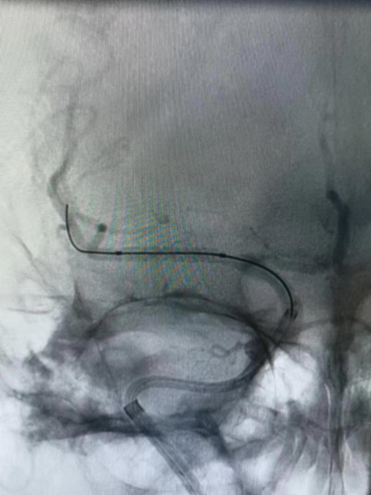

球囊通过病变。

球囊扩张过程。

扩张后造影。